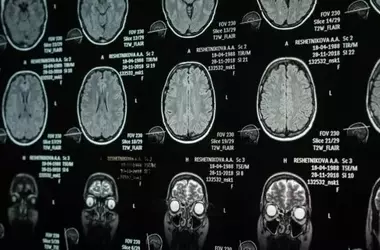

A recent neuroimaging investigation has unveiled unique brain activity patterns in adolescents afflicted with borderline personality disorder (BPD) as they engage in self-identity processing. This study illuminates the neural underpinnings of identity disturbance, a hallmark symptom of BPD, specifically in young individuals. The findings indicate a diminished activation in the dorsolateral prefrontal cortex, a critical region for cognitive regulation, suggesting a potential neurological mechanism behind the identity-related challenges experienced by these youth.

The study found that adolescents with borderline personality disorder showed markedly reduced activation in the right dorsolateral prefrontal cortex during tasks requiring self-reflection, contrasting sharply with healthy controls who displayed increased activity in this area. This particular brain region is fundamentally involved in executive functions and top-down cognitive control. The observed decrease in activation, or even deactivation, in BPD-affected youth suggests a compromised capacity for regulating self-related thoughts and processes. Such neurological differences underscore the profound challenges these individuals face in forming a stable sense of self, a core characteristic of their condition.

Moreover, the research identified diminished activity in other brain regions such as the left parietal cortex, the calcarine cortex, and the right precuneus during self-reflection in the BPD group. This broader pattern of altered brain engagement points to a more widespread neural dysfunction affecting various aspects of self-processing. Understanding these specific neural signatures provides crucial insights into the cognitive and emotional instability inherent in BPD, particularly the fluctuating goals, values, and self-image that define the disorder in its early stages. These findings emphasize the need for early and targeted interventions that consider these unique brain differences.